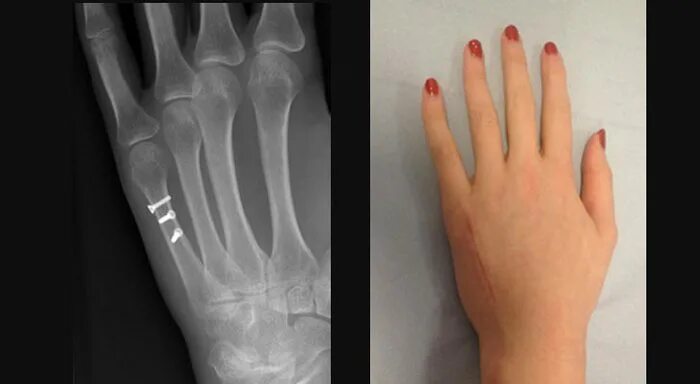

Ушиб лучезапястного